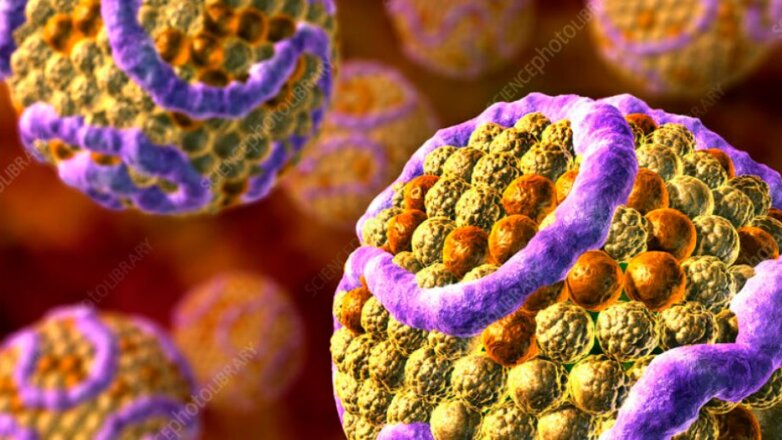

Τα αποτελέσματα της τρέχουσας μελέτης υποδηλώνουν ότι ακόμη και οι σχετικά χαμηλές συγκεντρώσεις PFAS στο αίμα σχετίζονται με δυσμενή προφίλ λιπιδίων του αίματος.